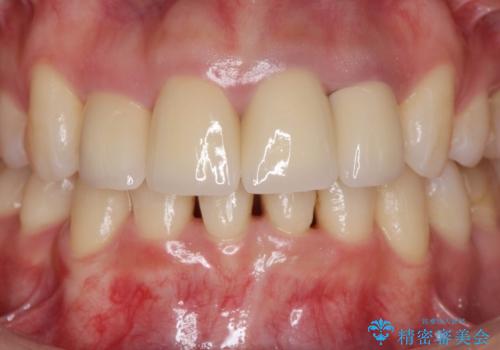

自然な歯の色に仕上げることができ、大変喜んでいただくことができました。